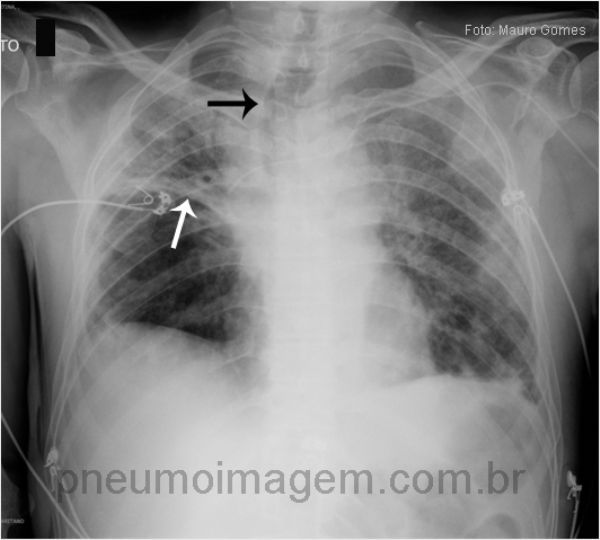

ASPERGILOSE INVASIVA

A Aspergilose Invasiva (AI) é rara e ocorre principalmente em hospedeiros imunocomprometidos. Neutropenia e uso prolongado de glicocorticoides são os fatores predisponentes mais comuns. AI leva ao óbito em 70-90 nos imun...